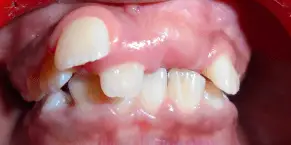

2 BY 4 APPLIANCE THERAPY

A 11 year old girl reported to the department with a complaint of irregularly placed upper front teeth. On clinical examination there was crowding in the maxillary anterior teeth and Angle’s Class I molar relation. Final diagnosis of Angle’s Class I molar relation with Dewey’s type 1 was proposed. A 2 by 4 appliance therapy was proposed in this case in which 4 MBT brackets were placed on the upper incisors and with 0.06 band material , banding was done on 16, 26 and 0.012 “ Niti wire was placed. In the first month an open coil spring was placed irt 11,21. A follow up of 6 months showed alignment of the upper anterior teeth and finally fixed lingual retainer were bonded.